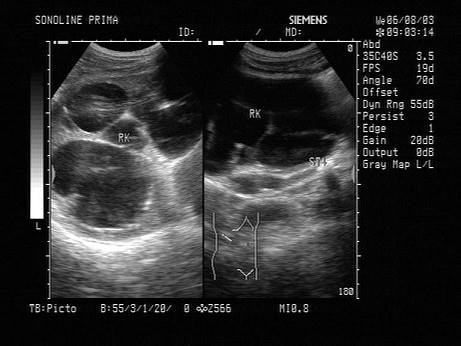

根据超声图像所示,判断致病人肾脏积水的梗阻在输尿管哪一段?(?)A.下段B.中段C.上段D.膀胱内E.肾盂内

问题 根据超声图像所示,判断致病人肾脏积水的梗阻在输尿管哪一段?(?)

选项 A.下段 B.中段 C.上段 D.膀胱内 E.肾盂内

答案 C